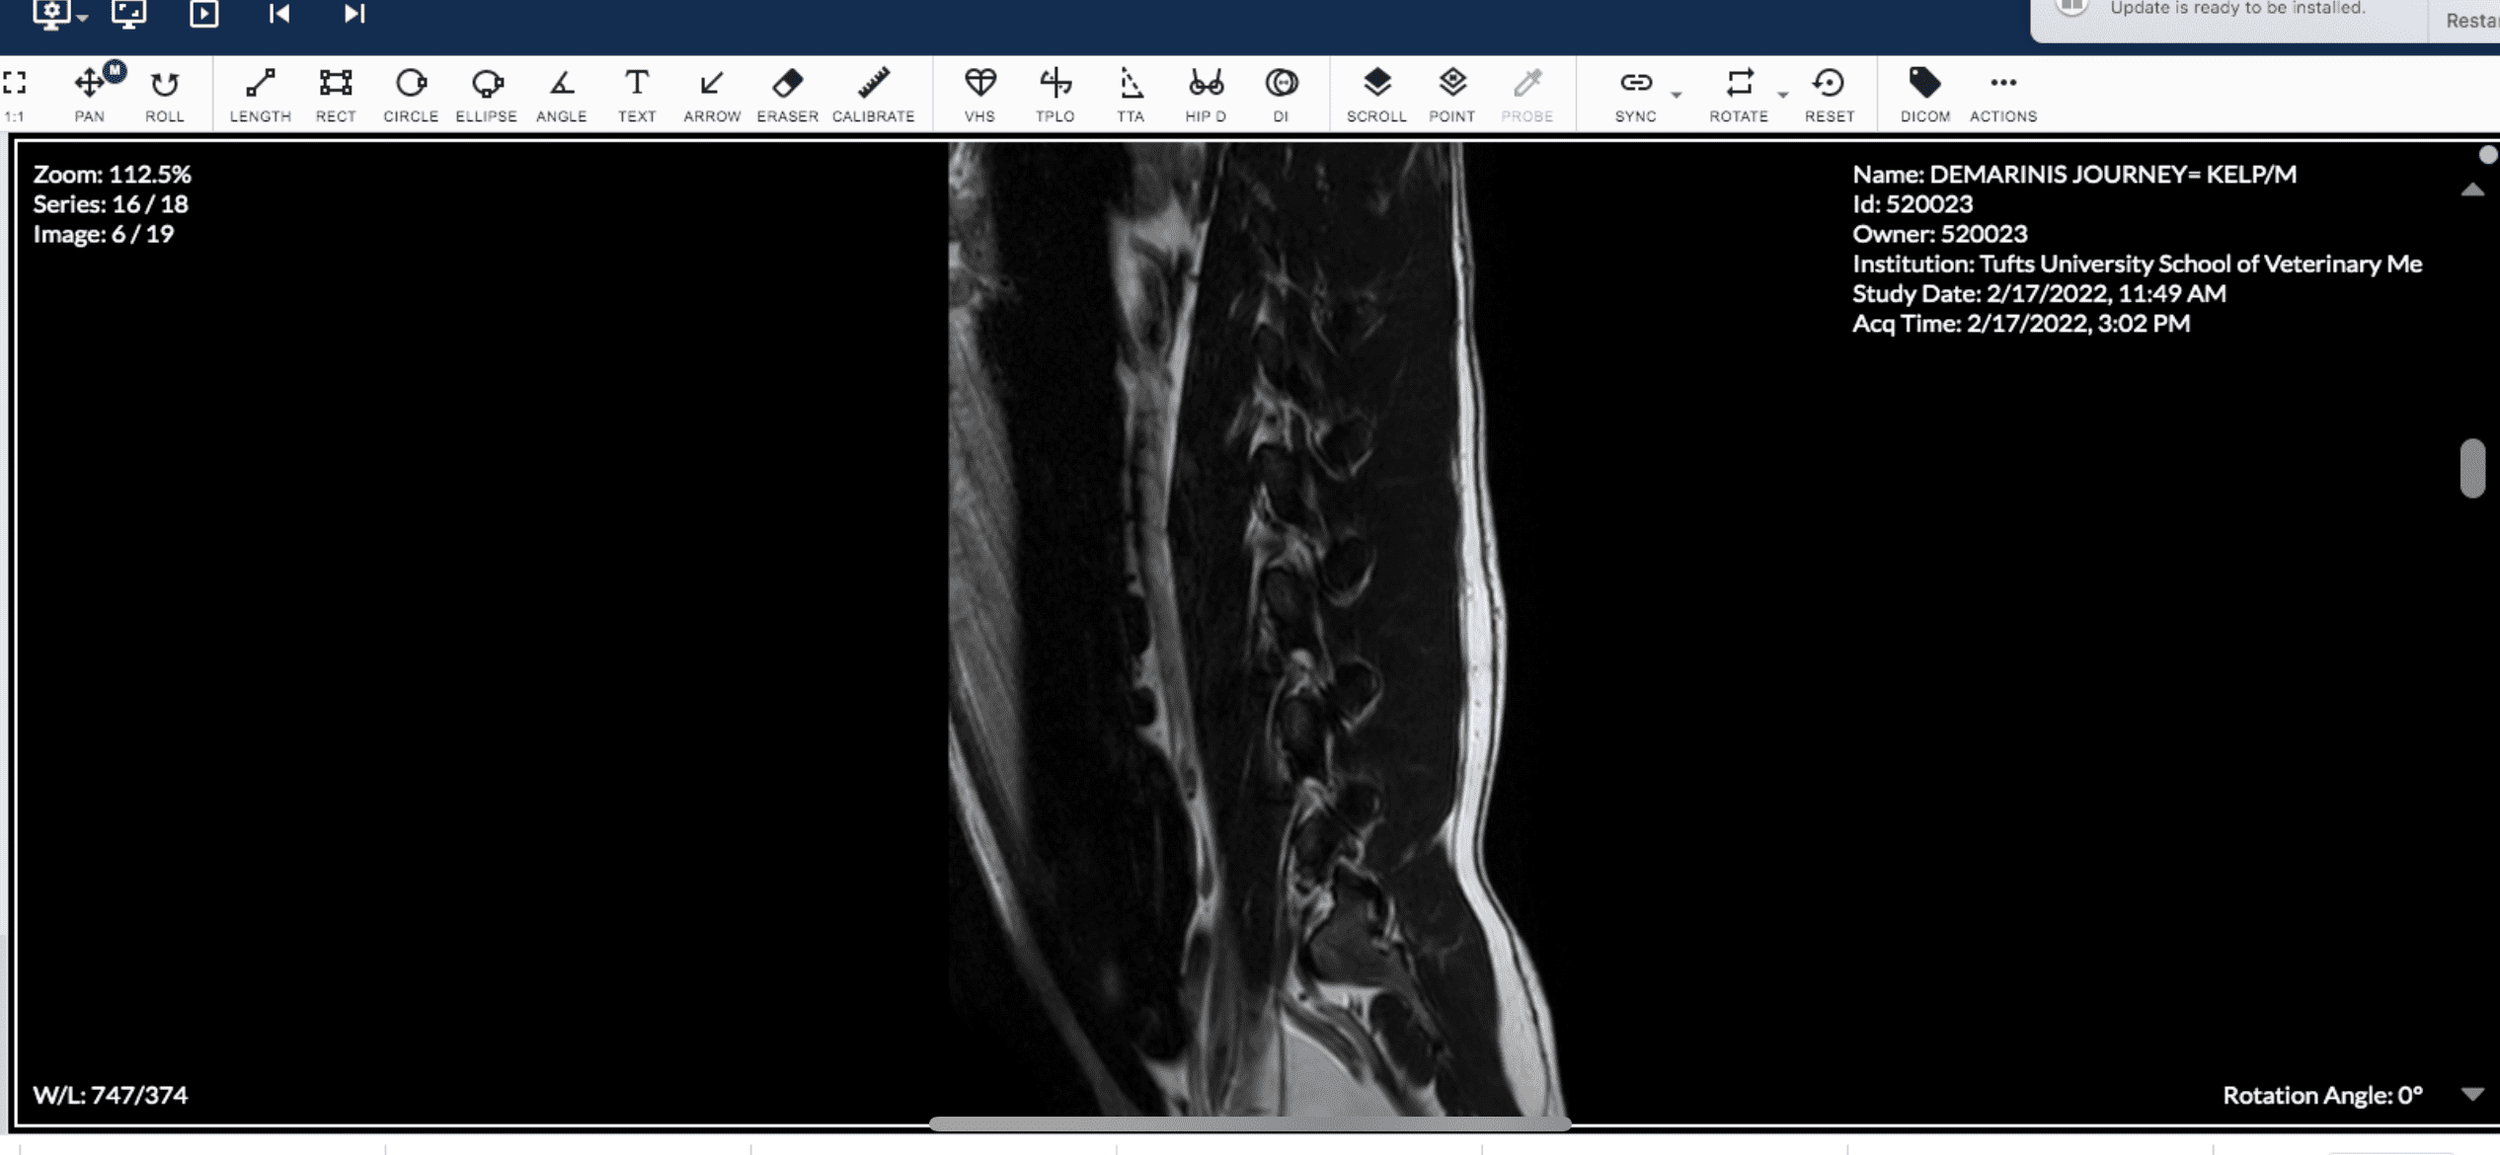

On 2/17/22 at 7:30am I dropped Journey off for his MRI. I was a nervous wreck. At 9:00am a vet technician emailed me asking for the video footage I had of Journey's episodes so that the board certified neurologist could take a look at them. At 3:30pm, the neuro resident called to update me. She said that the neurologist performing the MRI reviewed the videos as well as his brain scan. The brain scan was clear! Nothing abnormal showed up. BUT, the neurologist noticed after observing the videos that Journey seemed to display more of his episodes towards his lumbar/rear area, so the neurologist decided she wanted to do a lumbosacral MRI (an MRI of his lumbar/rear area). They identified that it was very possible he has a rare condition called Tethered Cord Syndrome. They couldn't rule out whether he also had Epilepsy, but based on the findings of the MRI, it seemed that the episodes Journey was having was related to Tethered Cord Syndrome.

Some of Journey's MRI Images of Tethered Cord

Screenshot of Journey's MRI Imagery